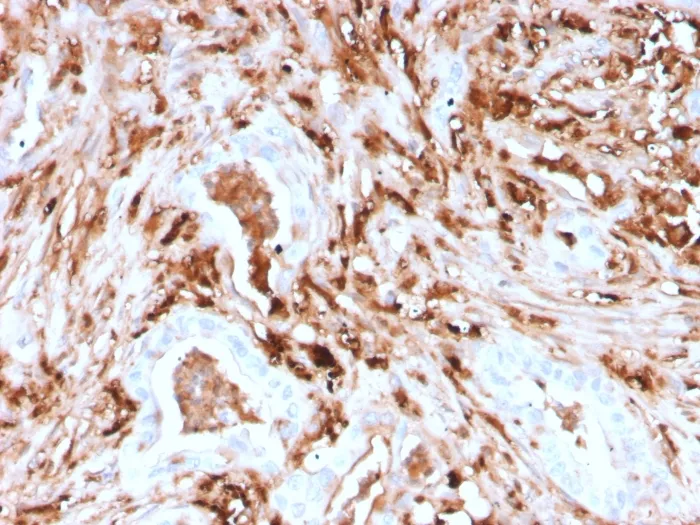

Anti-Ferritin, Light Chain (Node-Negative Breast Tumor Prognostic Marker)(rFTL/1388), CF740 conjugate

Anti-Ferritin, Light Chain (Node-Negative Breast Tumor Prognostic Marker)(rFTL/1388), CF740 conjugate

Mammalian ferritins consist of 24 subunits made up of 2 types of polypeptide chains, ferritin heavy chain and ferritin light chain. Ferritin heavy chains catalyze the first step in iron storage, the oxidation of Fe (II), whereas ferritin light chains promote the nucleation of ferrihydrite, enabling storage of Fe (III). Light chain ferritin is involved in cataracts by at least two mechanisms, hereditary hyperferritinemia cataract syndrome, in which light chain ferritin is overexpressed, and oxidative stress, an important factor in the development of ageing-related cataracts. Primary antibodies are available purified, or with a selection of fluorescent CF® Dyes and other labels. CF® Dyes offer exceptional brightness and photostability. Note: Conjugates of blue fluorescent dyes like CF®405S and CF®405M are not recommended for detecting low abundance targets, because blue dyes have lower fluorescence and can give higher non-specific background than other dye colors.Synonyms:

IHC, FFPE (verified) | WB (verified)Validated Applications:

IHC, FFPE, WBPositive Control:

HepG2, HeLa, HL-60 or 293T cells. Pancreas, Liver, Cerebellum or Testis.Concentration: